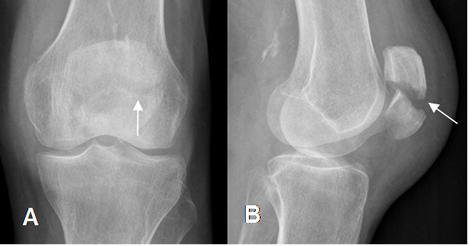

Fig 52 A. Fractura de patela.

A: Rx AP. Sutil imagen radiolúcida, en el borde superointerno de la patela.

B: TAC axial y C: TAC reconstrucción coronal. Se confirma fractura vertical y no desplazada de la patela.

Fig 52 B. Fractura de patela.

A: Rx AP y B: Rx lateral de rodilla. Fractura transversa, en el tercio medio de la patela, con prominencia de los tejidos blandos.